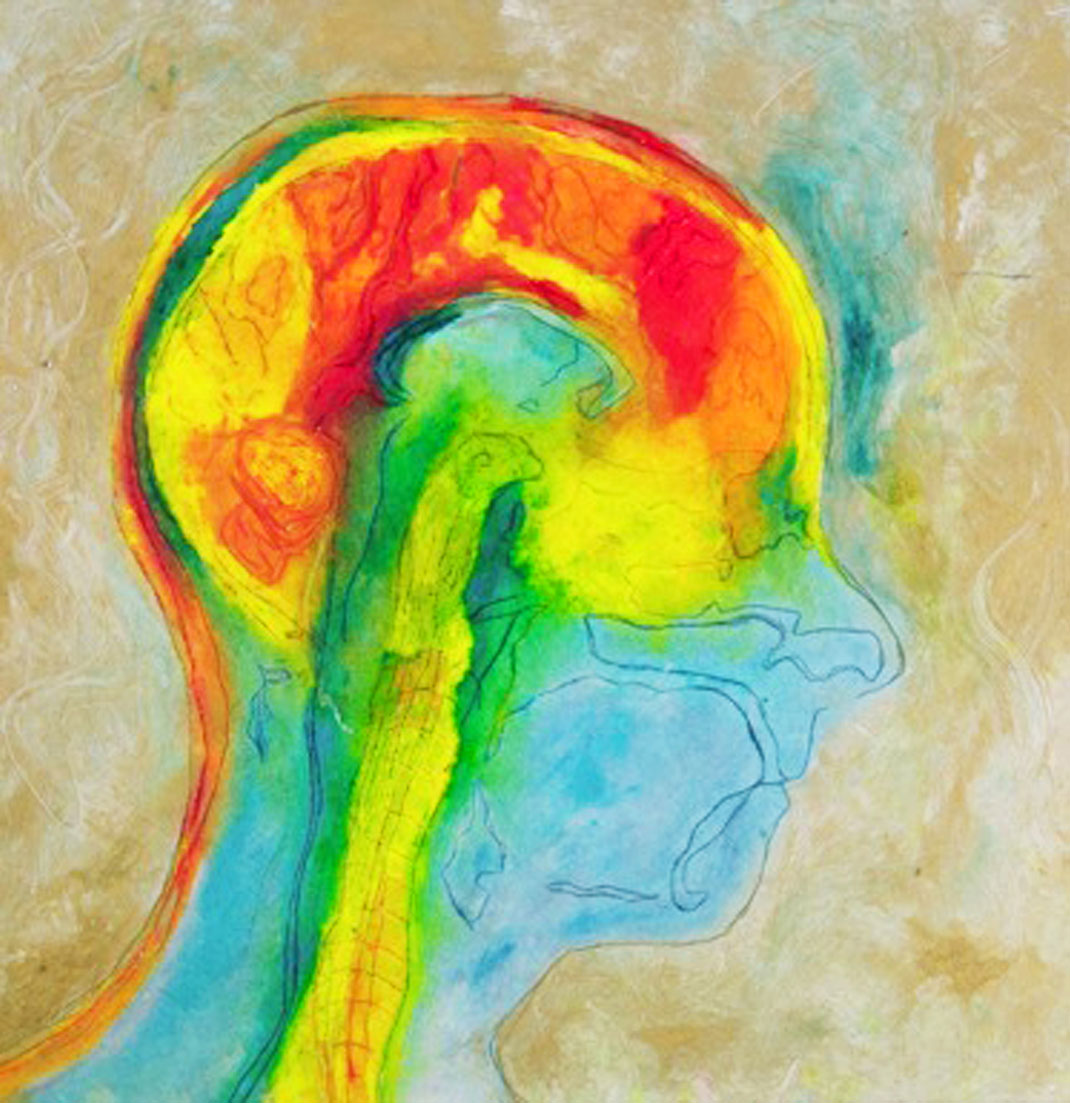

Elle trouve alors sa source d’inspiration dans sa maladie à travers ses IRMs. « Mes nombreux traitements m’ont donné envie de réinterpréter l’imagerie médicale. Les patients, souvent anxieux, ne voient que laideur et effroi dans les pixels noirs et gris des IRMs. J’ai alors ressenti le besoin vital de les utiliser pour montrer les merveilles et la beauté de nos cerveaux, y compris ceux souffrant d’une maladie. Je veux guérir les patients de la peur de regarder leurs IRMs », s’émeut Elizabeth.

En réutilisant ses scanners, Elizabeth Jameson cherche à insuffler des émotions et des sentiments dans la froideur technologique. Pour cela, elle utilise de nombreux supports : la peinture sur soie ou encore des impressions à partir de gravures sur cuivre ou sur plaque solaire. Ensuite, elle renforce la couleur de ses images grâce à de la peinture, des crayons ou du pastel sec. Le résultat offre une collection brillante, colorée, pleine d’émotion et de symbole.

Maintenant tétraplégique, Elizabeth crée avec l’aide d’un assistant. Selon elle, ses impressions ne sont pas qu’un moyen de faire la chronique des changements de son cerveau, qu’elle qualifie d’« organe le plus sacré ». Son travail est également un moyen de devenir plus familière avec ces changements, pour les rendre moins terrifiants. « Mon art est composé à 90 % de mon cerveau, tout simplement parce que je suis mon cerveau », conclut-elle.